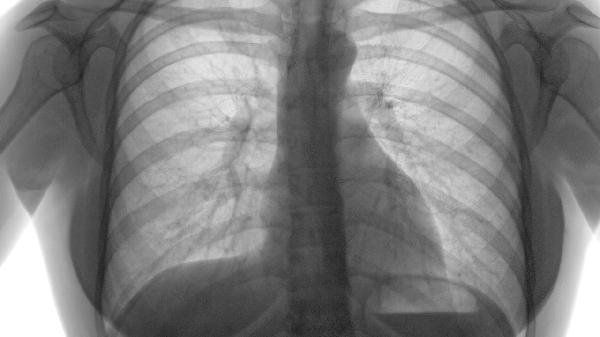

肺癌的预防和早期筛查对于肺气肿患者尤为重要。定期进行胸部CT检查可以发现早期肺癌,提高治愈率。戒烟是降低肺癌风险的最有效措施,同时避免接触二手烟和职业致癌物质。对于高风险人群,如长期吸烟者和肺气肿患者,医生可能会建议进行低剂量CT筛查。早期发现和治疗肺癌可以显著提高生存率,因此肺气肿患者应定期进行肺部检查,并密切关注任何新的呼吸道症状。